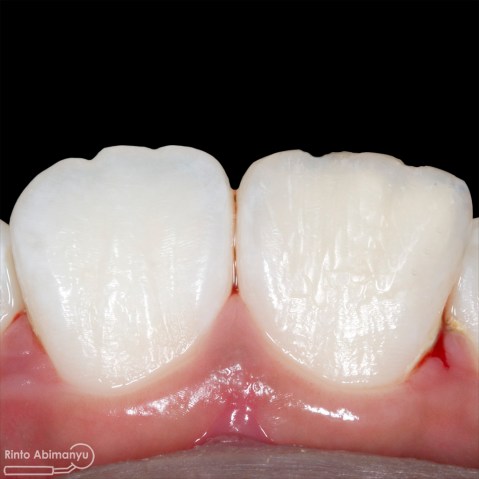

Setalah pengisian usahakan kamar pulpa dibersihkan dari sisa2 siler dan kotoran2 agar bahan adhesive yang kita pakai untuk restorasi dapat melekat maksimal.. Untuk basis saya menggunakan X-tra Base (Voco) kemudian diatasnya memakai komposit Z 350 XT (3M)…